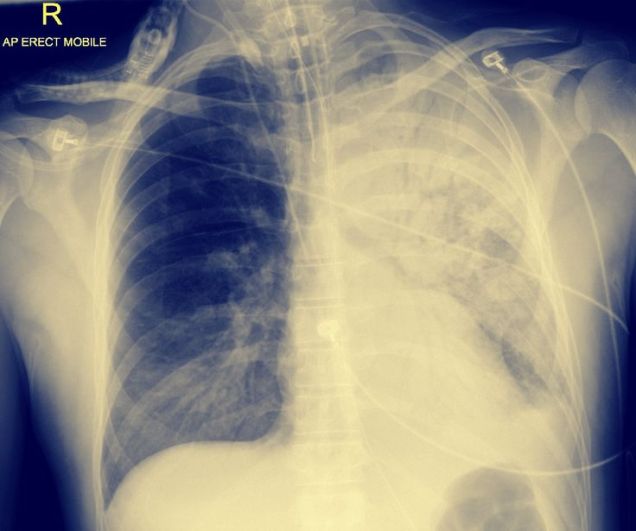

Lunginflammation kan ge överaktivering av immunförsvaret och en ökad mängd inflammatoriska cytokiner vilket i lungorna resulterar i vätskeansamling och försämrad syresättning av blodet. Jag har själv aldrig gett kortisonbehandling vid pneumoni förutom till KOL-patienter och astmatiker men nu kommer jag börja överväga det även hos andra patienter med pneumoni, som jag lägger in, om de saknar kontraindikationer.